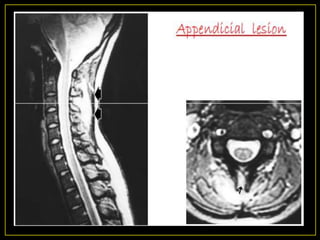

4) Appendicial lesion

• Isolated Pedicles & laminae (neural arch),

transverse processes & spinous process.

• Uncommon lesion (< 5%).

• ? In conjunction with the typical paradiscal Variant

• Radiographically - erosive lesions, paravertebral

shadows with intact disc space.

• Rarely, present as synovitis of facet joints.